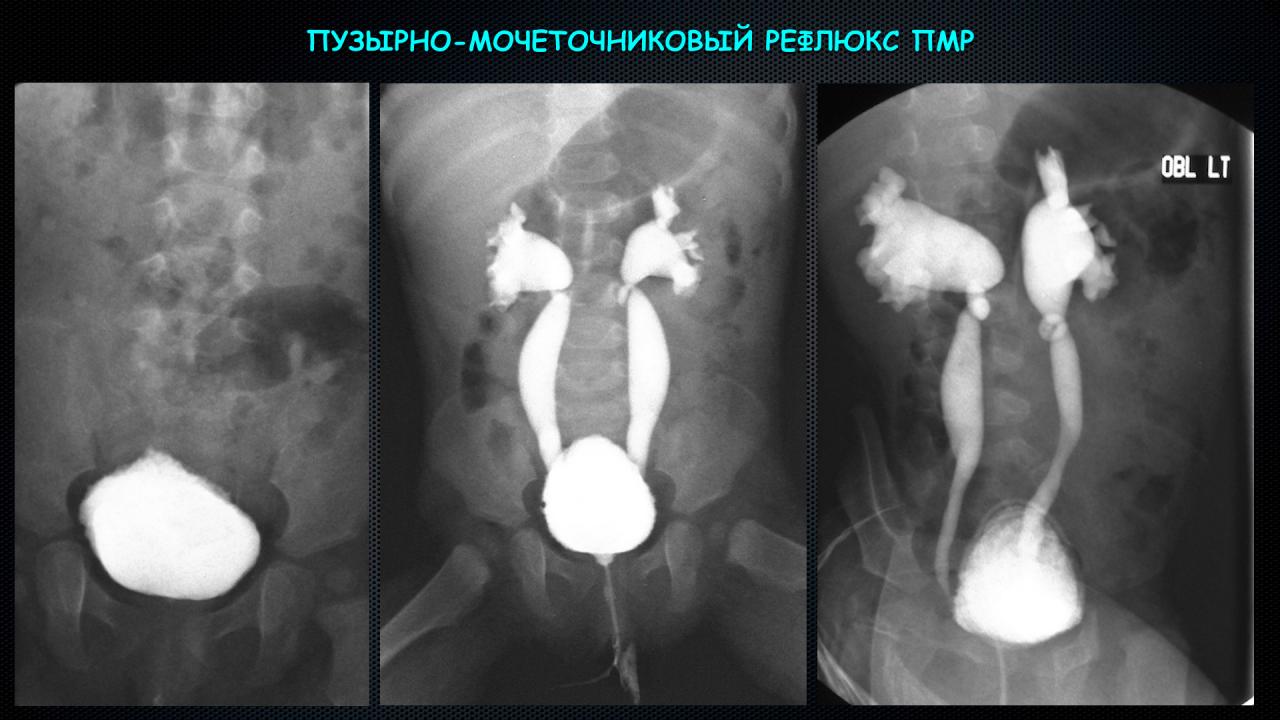

Медицинские изображения и примеры эксреторной цистографии